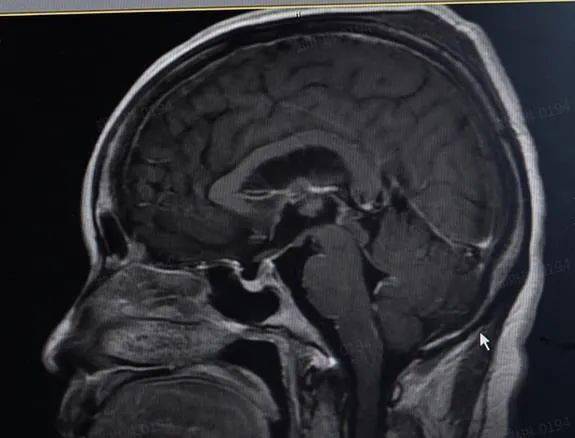

接诊医生结合患者的病史和体征 , 认为是颅内感染的可能性较大 。 最终 , 在患者的脑脊液及血清中找到了李斯特菌 , 进一步证实了医生的判断 。 给予抗感染等对症治疗后 , 陈女士的症状逐渐好转 。

【女子|女子吃了冰箱里的饭,高烧42℃,险丧命!只因忽视了它】医生在追问病史时了解到 , 患者在发病前两天 , 曾吃了聚餐时打包回来存放在冰箱的饭 。 “当时就觉得那个饭不大对劲 。 ”陈女士说 。 “怀疑是食用不卫生食物导致的细菌感染 。 ”医生介绍 , 李斯特菌病是危害最严重的食源性疾病之一 , 具有超强的“杀伤力” , 但是否会引起感染 , 取决于个体的年龄与免疫状况 。